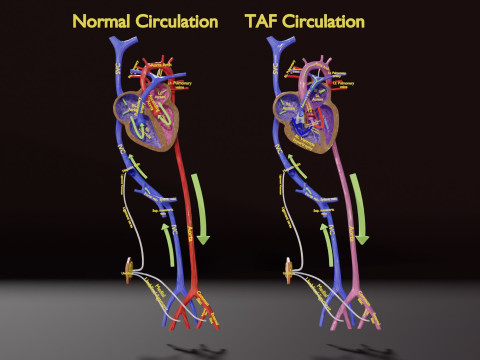

A blend model of brain along with its covering layers (meninges), skull bone and scalp labelled in detail and anatomically precise. The parts depicted are white, gray, pia, arachnoid, dura, bone, skin, fat, aponeurosis, periosteum, falx cerebri and more.